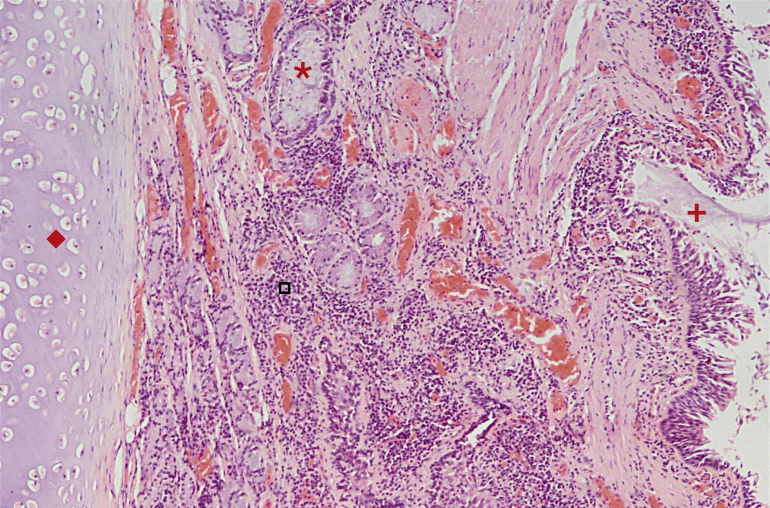

¿Qué está señalando la flecha verde?

Hiperplasia de las células calciformes

¿Qué está señalando la flecha azul?

Hipertrofia muscular

¿Qué está señalando la flecha negra?

Fibrosis subyacente a la membrana basal

¿Qué está señalando la flecha amarilla?

Inflamación eosinofílica